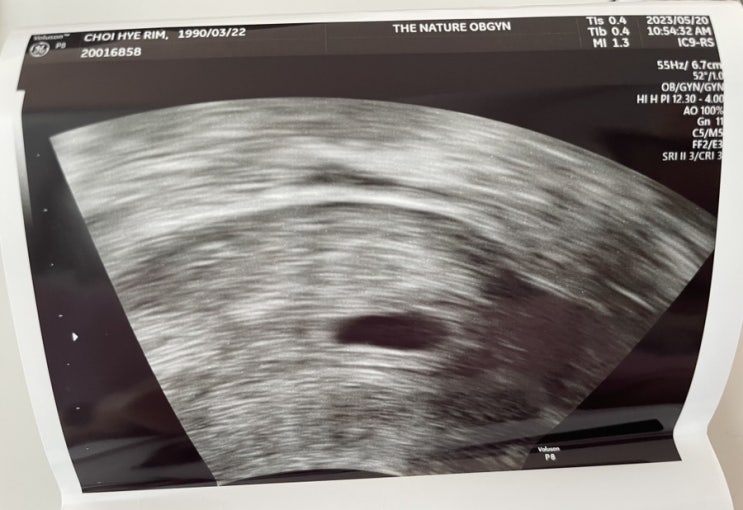

[임신일기] 임신 6주차 증상공유(태명, 심장소리, 배땡김, 빈뇨, 잔뇨, 배크기, 먹덧, 체덧, 증상 사라짐, 허리땡김, 부부 태몽)

5주차 아기집을 보고온 이후 자궁외임신이라는 걱정에서는 완전히 벗어났다. 우리 아기의 태명은 “뿜”이...

[임신일기] 첫 임신 계류 유산 후 재 임신 성공, 임신 초기 ~5주차 증상 공유(배테기, 임테기, 각종 초기 증상, 피검사, 초음파)

*쓸까말까 고민했지만 나와같은 걱정거리가 많은 임신 준비중인 분들에게 도움이 되고자 써보는 임신일기 2...